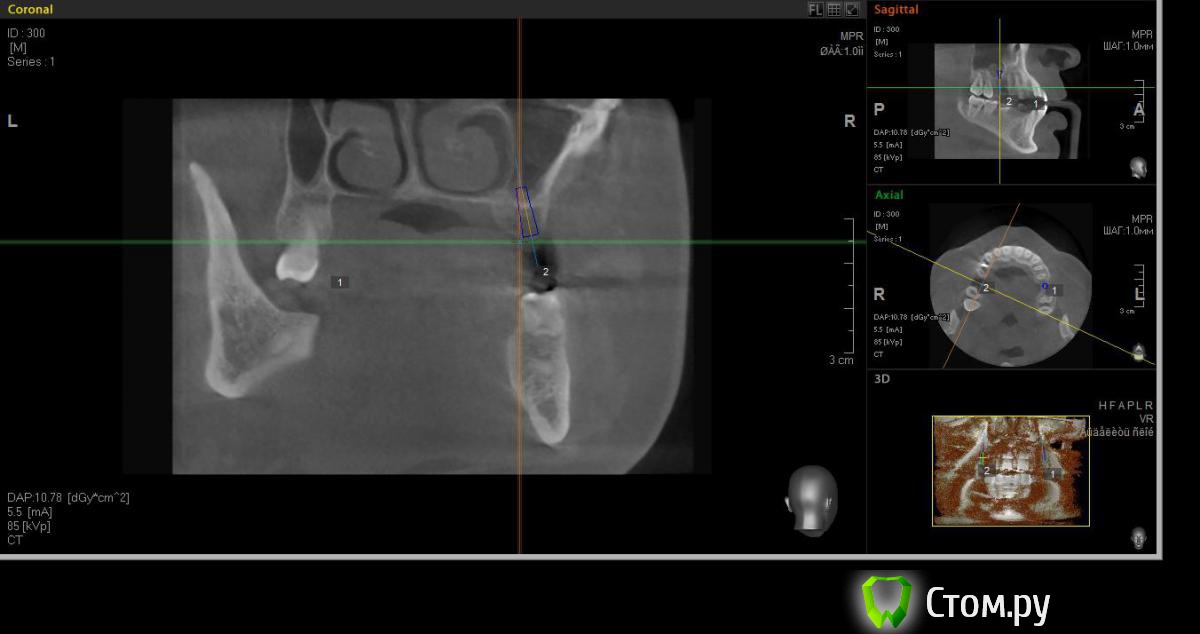

faity Опубликовано 18 мая, 2014 Автор Поделиться Опубликовано 18 мая, 2014 хочу вот так сделать, на 1.6 мягкий лифт, в обл 2.6 не лезтьвинты Ankylos 1.6- 4,5/11 2.6- 3,5/9,5кости в области 1.6- 7,5мм, должно хватить для закрытого, открытый пациент не потянет по финансам.какие мысли? Ссылка на комментарий

red_butler Опубликовано 19 мая, 2014 Поделиться Опубликовано 19 мая, 2014 Я бы не планировал хирургию исходя из финансовых пожеланий пациента, и 1.6 вел бы с открытым синусом. Представьте что при закрытом порвали мембрану, открытый придется делать, и за свой счет. Винт в позицию 1.6 поставил бы меньшего диаметра Ссылка на комментарий

red_butler Опубликовано 19 мая, 2014 Поделиться Опубликовано 19 мая, 2014 (изменено) Не знаю диаметры винтов в этой системе, между 3.5 и 4.5 Промежуточного нет?А 2.6 без синуса и диаметр больше Изменено 19 мая, 2014 пользователем red_butler Ссылка на комментарий

faity Опубликовано 19 мая, 2014 Автор Поделиться Опубликовано 19 мая, 2014 Не знаю диаметры винтов в этой системе, между 3.5 и 4.5 Промежуточного нет?А 2.6 без синуса и диаметр большепромежуточных к сожалению нета 2,6 больше не получитсяэто при ныненшнем радиусе и положении, если делать больше винт, то больше углублять, а тогда в синус провалюсь Ссылка на комментарий